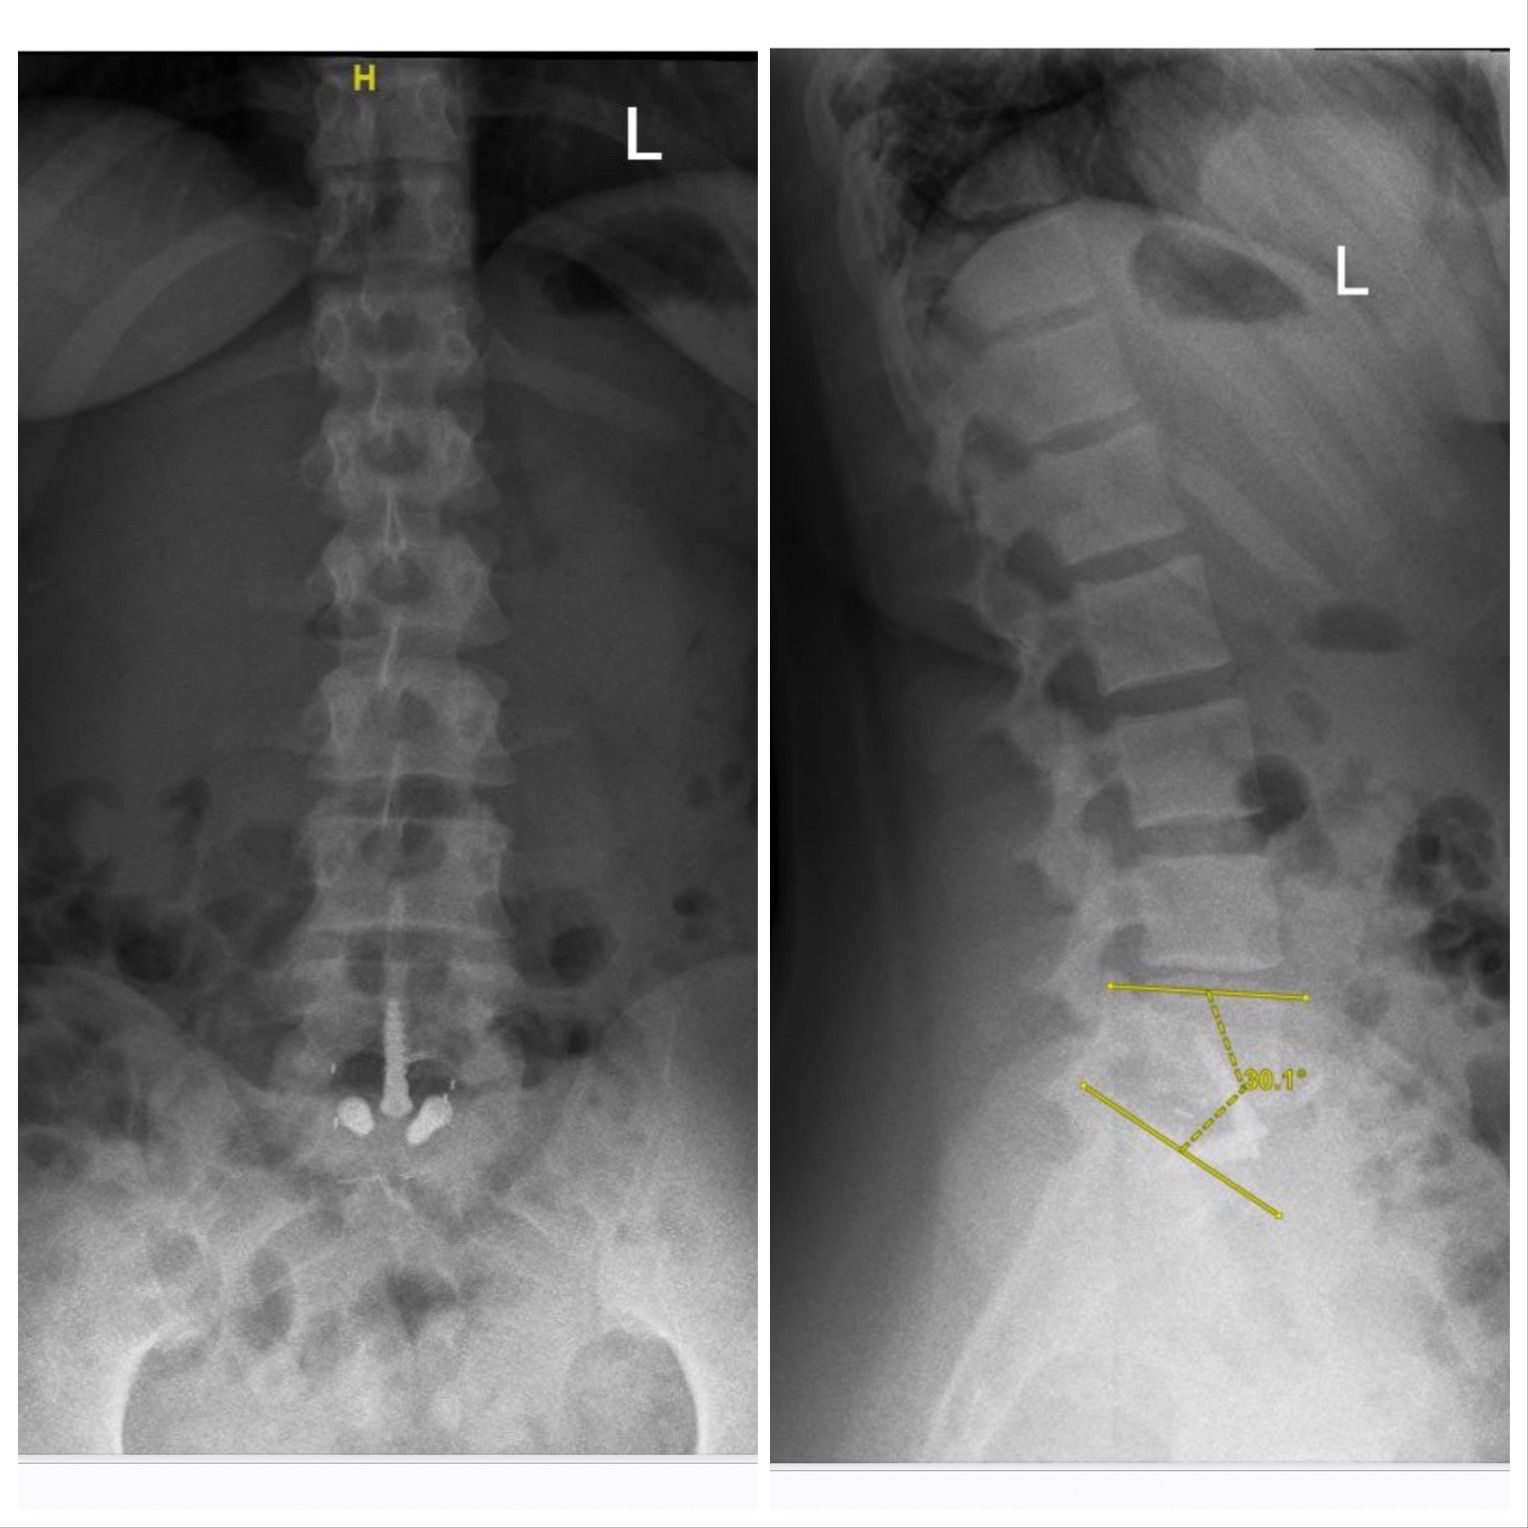

أجرى فريق طبي بقيادة أستاذ مساعد جراحة المخ والأعصاب والعمود الفقري بمستشفى الملك فهد الجامعي بالخبر التابع لجامعة الإمام عبدالرحمن بن فيصل، الدكتور سلطان السالمي، عملية تغيير لغضروف الفقرات القطنية عن طريق البطن لشابة تعاني من الآلام أسفل الظهر تبلغ من 28 عامًا.

وتابع أن هذه العملية تعد من العمليات المعقدة خاصة أن المريضة كانت تعاني من الآلام منذ خمس سنوات، وتمكنت من إجراء العملية وتماثل المريضة للشفاء وذلك بتقنية حديثة لمعالجة الآلام الظهر المزمنة وقد استغرقت مدة العملية ساعتين.

ولفت الدكتور السالمي إلى أن نجاح العملية يعود لما يتمتع به مستشفى الملك فهد الجامعي بالخبر من تقنيات حديثة في كافة التخصصات، ومنها تخصص جراحة العمود الفقري إضافة إلى الكوادر الوطنية المؤهلة.